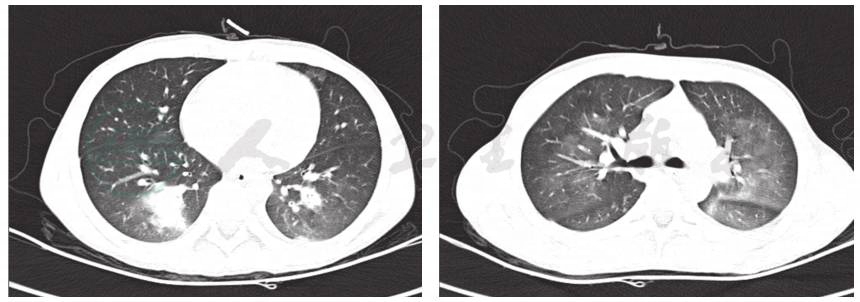

辅助检查:血常规:白细胞计数10.3×109/L,中性粒细胞百分比84.2%,淋巴细胞百分比8.3%,红细胞计数4.36×1012/L,血红蛋白126g/L,血小板 150×1012/L;CRP 87.2mg/L;降钙素原7.22ng/ml;DIC基本正常;肝功能正常;痰培养未见细菌真菌生长;血培养未见细菌生长;6天前肺CT显示双肺多发渗出,以右肺下叶为主伴有实变,双侧胸腔积液(图1);入院前1天肺CT显示双肺下叶实变范围较前增大。双侧胸腔、右侧叶间积液较前减少(图2)。

图2 入院前1天肺CT